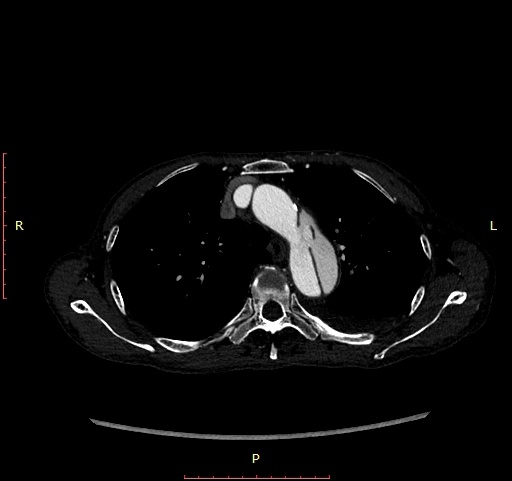

接診後,教授團隊仔細分析了患者的CTA影像資料,發現問題並不簡單,患者主動脈夾層第一破口位置距離左鎖骨下動脈不足1.5cm,而足夠的錨定區長度是保證此類手術成功,術後不發生I型內瘻等嚴重併發症的關鍵。更大的問題是,該患者為透析患者,而左鎖骨下動脈恰好是患者透析使用的自體動靜脈內瘻的供血動脈。若覆蓋左鎖骨下動脈,雖可獲得足夠的錨定區,但需要犧牲掉患者左上肢賴以生存的“生命線”,且可能影響脊髓供血動脈,增加術後截癱風險。

無足夠的錨定區,就需向近端延長錨定區,如何延長錨定區成為面臨的現實問題。延長錨定區的方法可選擇胸主動脈支架體外“開窗”、原位“開窗”及左頸總動脈-左鎖骨下動脈轉流術(覆蓋左鎖骨下動脈)。另外,夾層遠端存在第二裂口,且遠端錨定區血管重塑不佳,需延長遠端錨定區覆蓋第二枚支架。